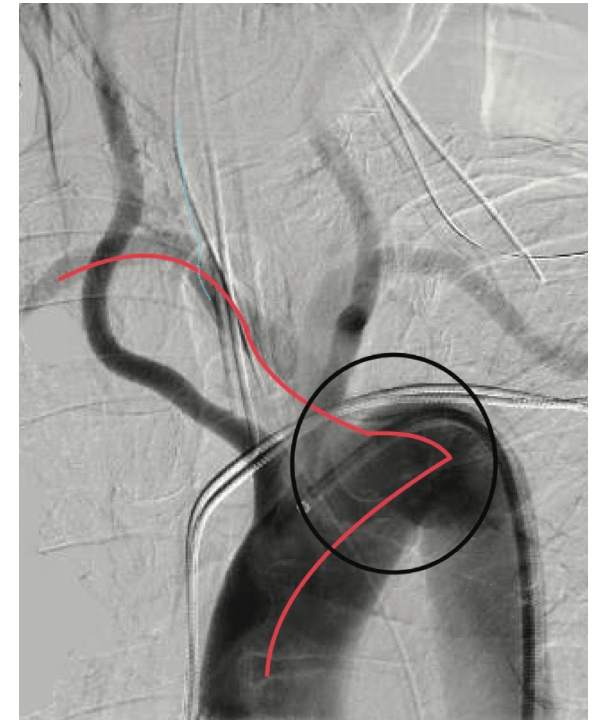

Radiographically, all have a similar appearance (Figures 5-8). They move left across the trachea, well into the lung field, and make an acute trajectory change back to the right, towards the transverse and ascending aorta. This abrupt course of the catheter change resembles a “shark’s tooth” and as a radiographic sign, may offer the clue of an aberrant subclavian. Different wires may enable easier negotiation into the ascending aorta. Wholey wires (Medtronic) may be used because of their soft tip and strong shaft. Hydrophilic wires such as Glidewires (Terumo) are also used to navigate through the aberrancy. Keeping an Amplatz super stiff wire in the catheter may help provide the necessary support for selective coronary angiography. Even if operators get close to the coronary ostia, tension and energy built up in the catheter can disallow selective engagement and force a bailout to the contralateral radial or the femoral approach. Conversely, there are times in the presence of this ominous anatomy when catheters will engage quicker than the operator can do a “time out.” A skillful operator might display some “catheter legerdemain” to negotiate these problems; however, a little bit of luck also goes a long way. One doesn’t necessarily have to be a funambulist to recognize and selectively cannulate the coronaries.

Rare as it is, arteria lusoria is a menacing obstacle for an interventional cardiologist or any operator that is utilizing a right radial approach. If known prior to procedure, an ultrasound-guided femoral or left radial approach should be used to potentially reduce contrast dose, as well as operator and patient radiation dose. This approach might also preserve the operator’s mental capital if the procedure becomes time-consuming. If the anomaly is unknown to the operator, the “shark’s tooth” sign could identify the aberrancy on initial catheter passage promptly. If the operator struggles with selective engagement, identification of the aberrant subclavian can ameliorate the course of the procedure for the better.